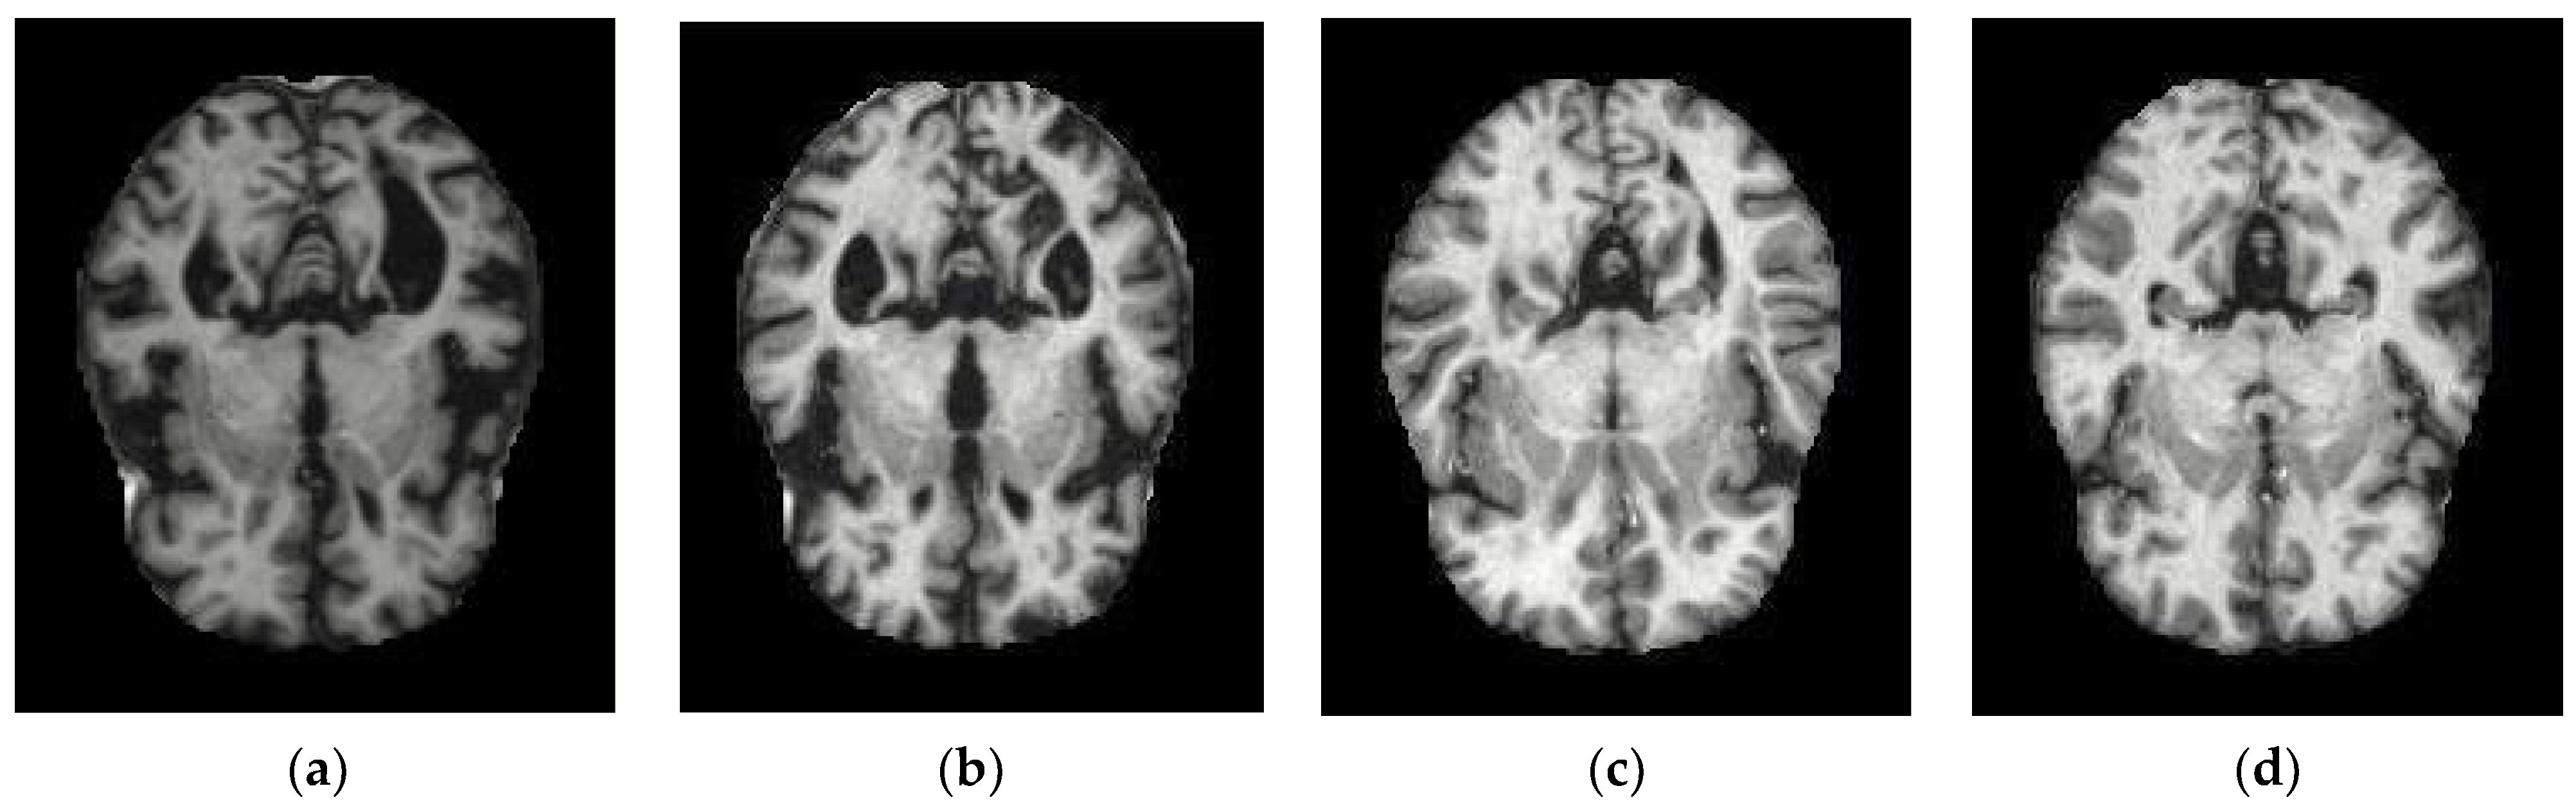

| Conv_1 | ![]() | ![]() | ![]() | ![]() |

| Conv_2 | ![]() | ![]() | ![]() | ![]() |

| Conv_3 | ![]() | ![]() | ![]() | ![]() |

| Conv_4 | ![]() | ![]() | ![]() | ![]() |

| Conv_5 | ![]() | ![]() | ![]() | ![]() |